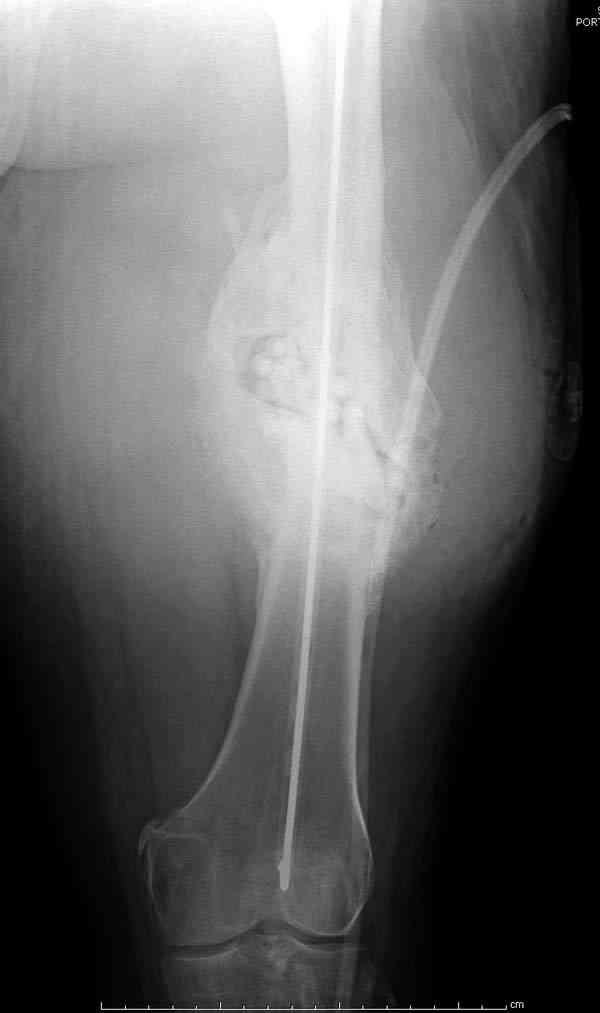

На ренгенограмме явный остеомиелит с секвестром, секвестерэктомия из медиального доступа и замена старого антибиотического гвоздя на новый.

После трех дней ваккуумного дренажа, из латерального доступа удаление остатков старых антибиотичеких бус, закрытие медиальной раны с наложением ваккуумирования латерально. В следующий раз, через пару дней надеемся закрыть рану.

7-8 послеоперационные